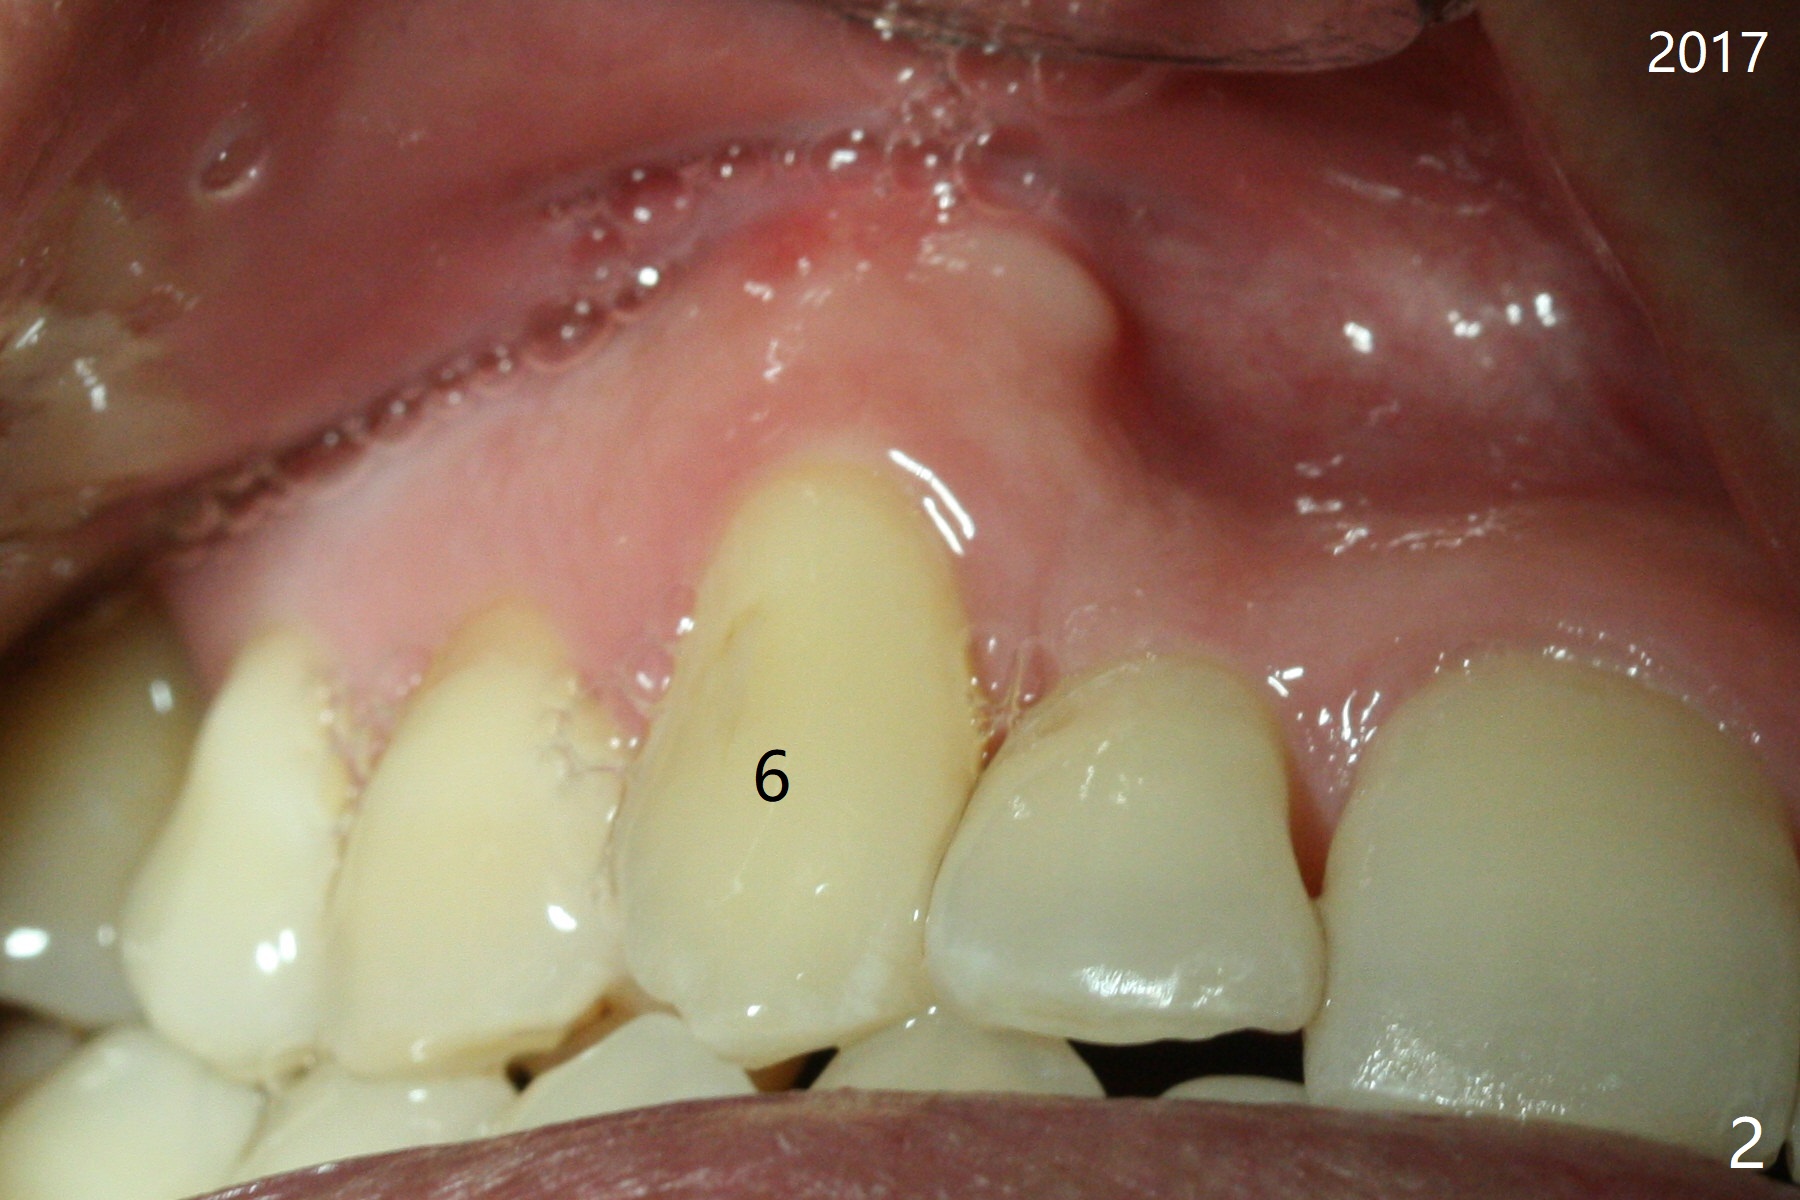

A 45-year-old man had severe malocclusion and chose non-extraction orthodontic treatment (Fig.1 (2012)). Five years later, the tooth #11 discolors (Fig.3, as compared to #6 in Fig.2). Immediately after RCT (Fig.4,5), the affected tooth has sudden change in shade (Fig.6). Two weeks later there is rebound in shade (Fig.7). The latter improves after two rounds of chair-side internal bleaching with 35% Hydrogen Peroxide for 20 minutes and build-up with the lightest shade composite (Fig.8). For optimum, place the bleach gel in the pulpal chamber and close the access with Cavit for a few days. In fact the latter is unnecessary. The treated tooth looks as normal as the tooth on the other side 1 year 10 months post whitening (Fig.9). PARL reduces 3 years post RCT (Fig.10 <, as compared to Fig.5).